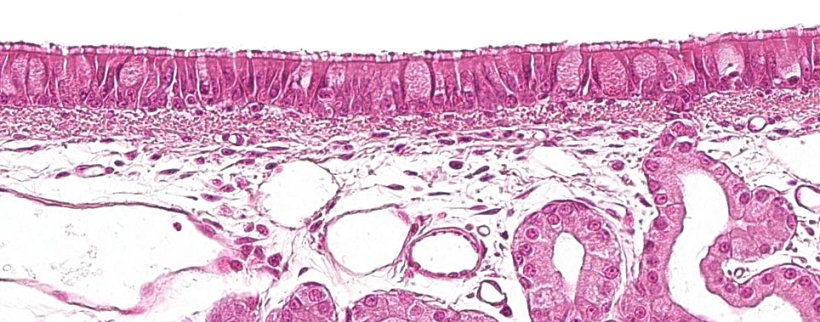

La primera parte del aparato respiratorio, la porción conductora o vías respiratorias, va desde la cavidad nasal hasta las últimas ramificaciones de los bronquiolos, e incluyen además a los senos nasales y paranasales que están conectados con la cavidad nasal, la nasofaringe y la laringe. Todas estas estructuras tubulares están revestidas por un epitelio seudoestratificado ciliado con células caliciformes (figura 1), responsable de uno de los principales sistemas de defensa de la mucosa respiratoria, el aparato mucociliar. Este sistema lo conforman los cilios de las células del epitelio respiratorio, junto con las secreciones de las células caliciformes y las glándulas seromucosas que aparecen bajo la mucosa respiratoria y su principal función es eliminar las partículas que entran a través del aire inspirado. Las glándulas secretan un líquido claro, poco viscoso y rico en proteínas que se dispone entre los cilios conformando un medio que favorece el movimiento de estos en sentido ascendente. El moco que secretan las células caliciformes se deposita sobre los cilios y permite la adherencia de las partículas inhaladas. El movimiento ascendente de los cilios empuja el moco hacia la parte superior del aparato respiratorio, que puede ser deglutido y pasar al aparato digestivo, donde es digerido, o ser expulsado al exterior a través de la boca y/o la cavidad nasal. Agentes como Mycoplasma hyopneumoniae, que provoca la pérdida de los cilios, o virus como el de la gripe porcina o el coronavirus respiratorio, que provocan la destrucción de las células epiteliales, llevan a cabo su acción patógena destruyendo este sistema defensivo.